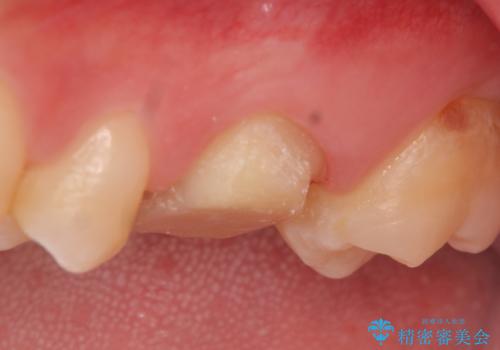

- 3日ほど前から何もしなくても左上奥歯がズキズキ痛むので診て欲しいといらっしゃった方の症例です。

検査の結果左上6に持続痛を認めたため根管治療を行い、症状の緩解を確認後オールセラミッククラウンによる補綴を行いました。